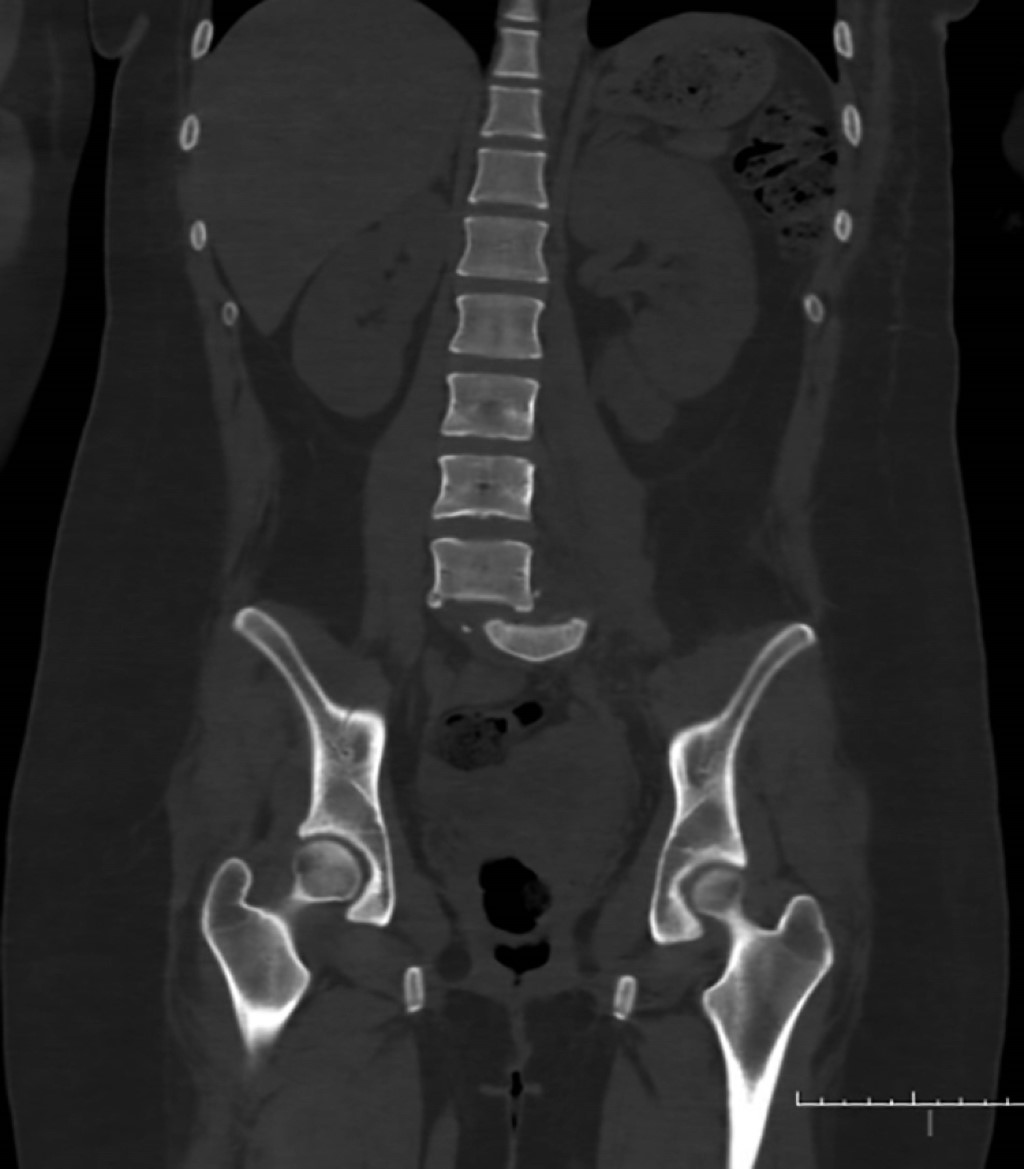

Inicia su padecimiento actual el día 5 de febrero de 2024 a las 23:00 horas al sufrir accidente vehicular como copiloto; refiere salir eyectada del vehículo al impactar contra objeto en carretera, con pérdida inmediata del estado de alerta. Atendida de manera inicial en hospital regional o por presentar trauma cerrado de abdomen que requirió laparotomía exploradora, así como hemotórax el cual se manejó con tubo endopleural. Se decide traslado a nuestro hospital de tercer nivel por presentar fractura luxación de L5-S1; ingresa a nuestro servicio el día 18/02/24. A la exploración física dirigida al ingreso se encuentra lo siguiente: extremidades superiores izquierda y derecha íntegras, con fuerza muscular valorada en escala de Daniels 5/5 en todos los grupos musculares principales y sensibilidad 2/2 en todos los dermatomos. Extremidad inferior derecha íntegra, con fuerza muscular valorada por escala de Daniel 5/5 en todos los músculos clave, sensibilidad 2/2. Extremidad inferior izquierda íntegra, con fuerza muscular valorada por escala de Daniels 5/5 en grupos musculares clave, con función motora a nivel de flexoextensión de pie y tobillo en 0/5 con dermatomo afectado L5-S1 en 1 de 2 sin poder discernir en prueba pica y toca. Se realizan estudios de imagen de manera inicial a su ingreso en unidad de politrauma, reportan lo siguiente: en radiografía anteroposterior (Rx Ap) y lateral de columna dorsolumbar se observa alteración en la congruencia articular a nivel de L5-S1 con desplazamiento en sentido coronal hacia lado derecho de columna vertebral (Figura 1). Tomografía axial computarizada (TAC) simple de pelvis en la que, en corte sagital coronal y reconstrucción 3D, se observa falta de congruencia articular a nivel de L5-S1 con traslación coronal hacia la derecha sobre el sacro, solución de continuidad ósea a nivel de 5 apófisis transversas de lado izquierdo desde L1 a L5 (Figuras 2 y 3). Se decide ingreso a cargo del Servicio de Ortopedia con diagnóstico de fractura luxación L5-S1 AO 53C TLICS 8 puntos Asia B.